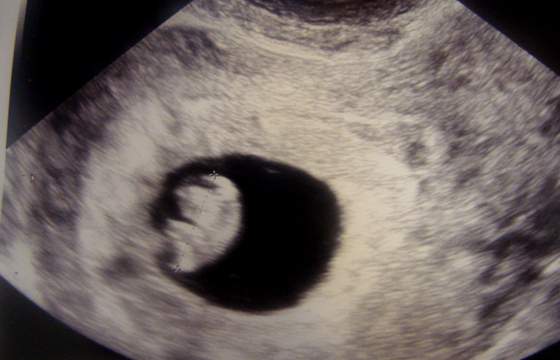

U nas dobrze. Fasolinka rośnie, ma już 9,9mm i serduszko bije. Mam luteinę, magnez i witaminki i tonę badań na 19 czerwca ;)

a oto mój okruszek : DSC06414.jpg

• DSC06414.jpg

DSC06414.jpg

20,6 KB · Wyświetleń: 31